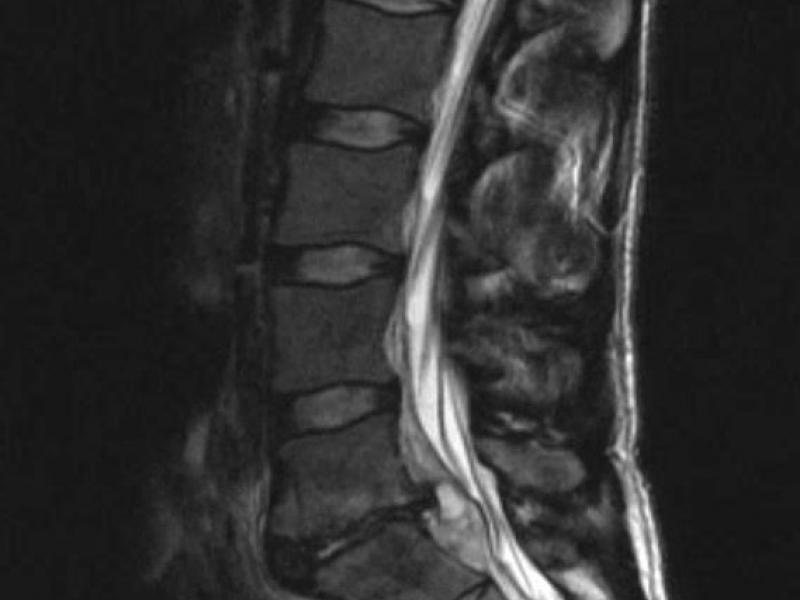

A 30 yo M presents to the ED complaining of atraumatic lower